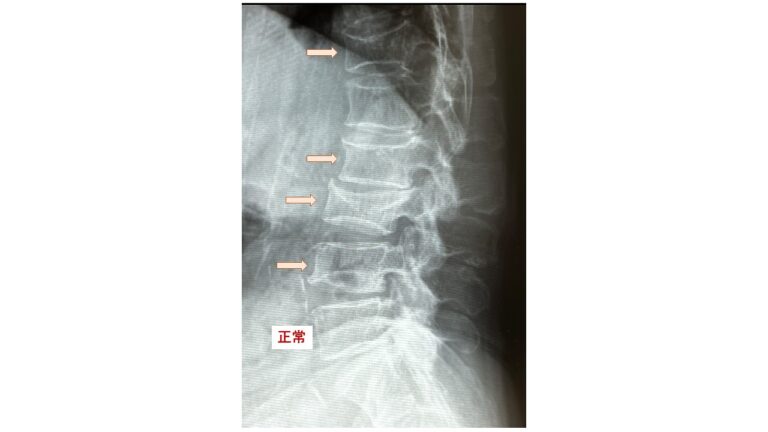

2)X線圧迫骨折の定義:左から2番の脊椎X線像で、B/A=80%以下、C/A=75%以下が圧迫骨折。圧迫骨折=高度の骨粗鬆症を意味します。

正常脊椎X線